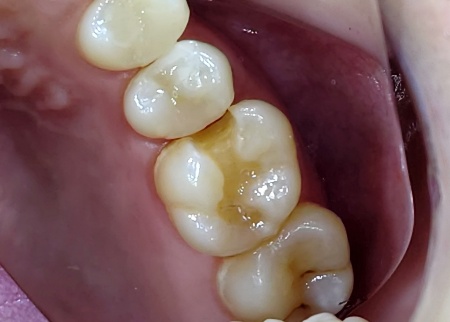

治療前

拝見したところ、左上奥歯1本は手前の歯と隣接している面から噛み合わせの面にかけて、虫歯が生じていました。 このまま放置すると、虫歯が神経に達して今より強くしみるようになったり、痛みが出たりするリスクがあるため、早急に治療する必要があると診断しました。 |